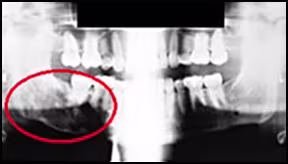

Excessive Exposure Examples:

Images demonstrating how excessive exposure can lead to failure to detect pathologic features. The image on the right is a digitally enhanced version of the left overexposed panoramic radiograph and clearly demonstrates the appearance of a radiolucent region causing expansion and thinning of the inferior cortex of the right mandible – features that were not evident on the original.

Figure 29A. Original Panoramic Image.

Figure 29B. Enhanced Panoramic Image